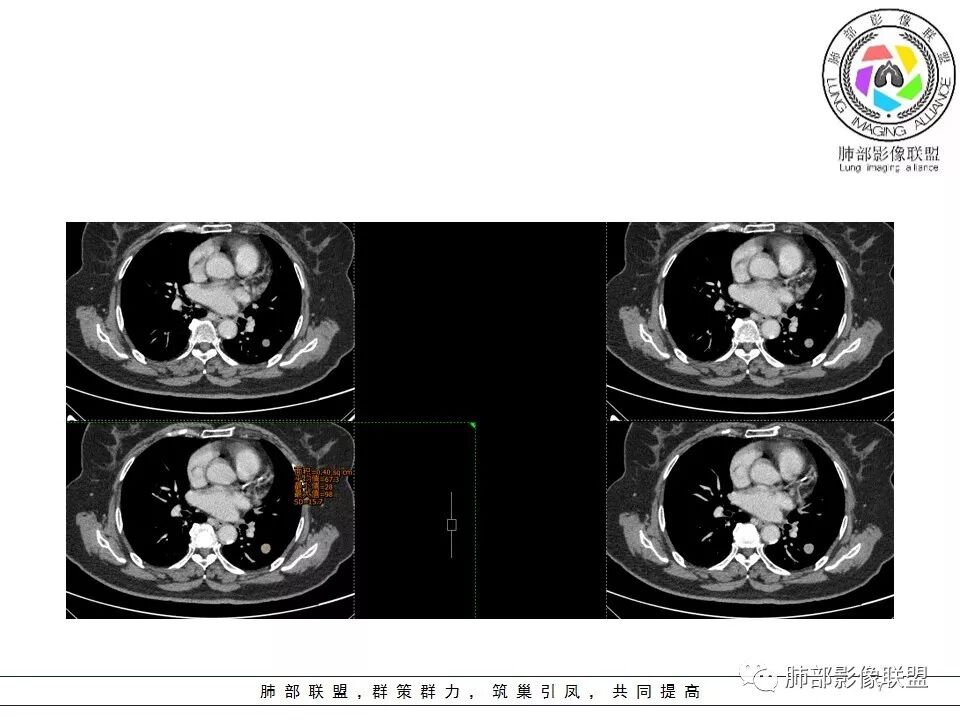

定位 左肺下叶背段斜裂旁实性小结节,边界清晰,密度尙均匀,未见脂肪钙化,与支气管关系不密切,可见肺血管贴边,增强呈轻中度强化,平扫47hu 动脉期48 静脉期67hu,

定性 常规考虑 良性结节,错构瘤或PSP可能,鉴别类癌,神经源性肿瘤,巨淋巴结增生,建议追观或穿刺活检。

CT值46H

增强67HU

动脉期弱一些,后期强化明显一些

动脉期边缘斑点状、结节状强化为主

后期趋向于均匀强化

动脉期测量区域——中央,不是强化区域

其实强化还算是中度,幅度超过20HU